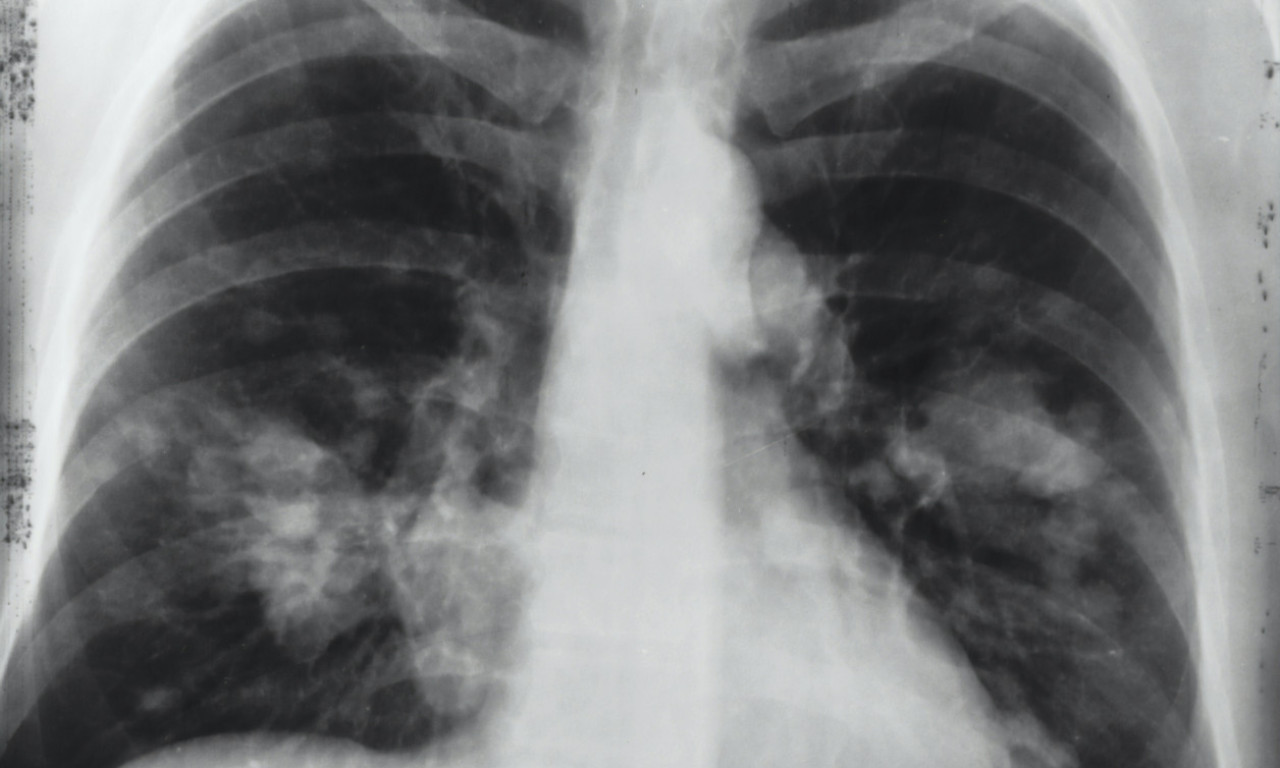

Bora je preminuo u bolnici u Ljubljani, gde je bio smešten zbog ozbiljnih problema koje je imao sa plućima.

Frontmen grupe "Riblja čorba" hospitalizovan je zbog komplikacija uzrokovanih hroničnom obstruktivnom bolešću pluća